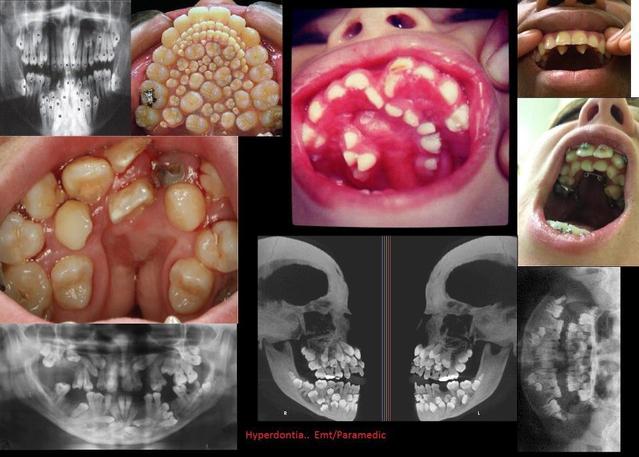

09.05.2013 - 16:11:14 <anon> HOLY FUCKING SHIT KILL IT WITH FIRE WHAT THE HELL MAN

09.05.2013 - 16:13:44 <anon> Voi vittu... menin sitten googlettamaan hyperdontia

09.05.2013 - 18:13:14 <anon> Hammaslääkärinä näen tällaisia tapauksia muutaman kerran kuukaudessa. Aina ne eivät kuitenkaan ole näin pahoja.

10.05.2013 - 04:22:44 <anon> It's called supernumerary teeth http://supernumeraryteeth.com/